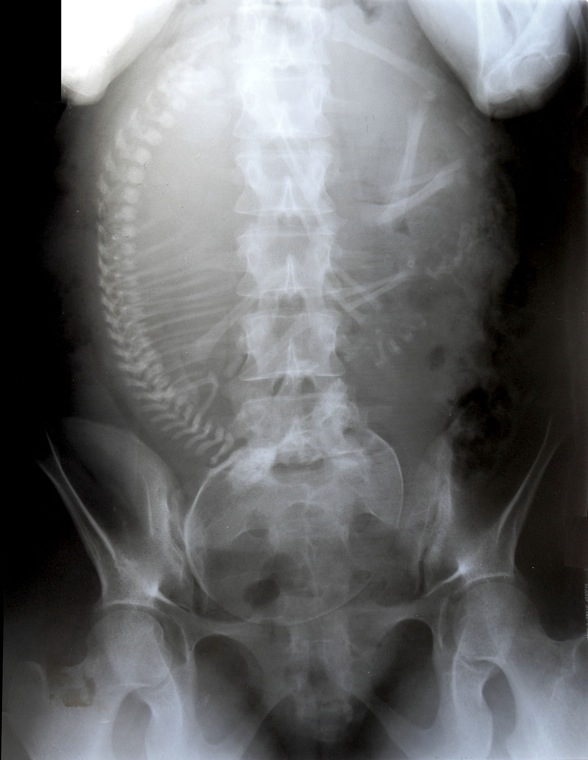

Analyse de radiographies

Radiologie

Analyse différentes radiographies. Essaye de reconnaître:

les différentes parties représentées: os, articulations,...

les malformations, les déplacements, les fractures.

l’âge des sujets: zones de croissances.